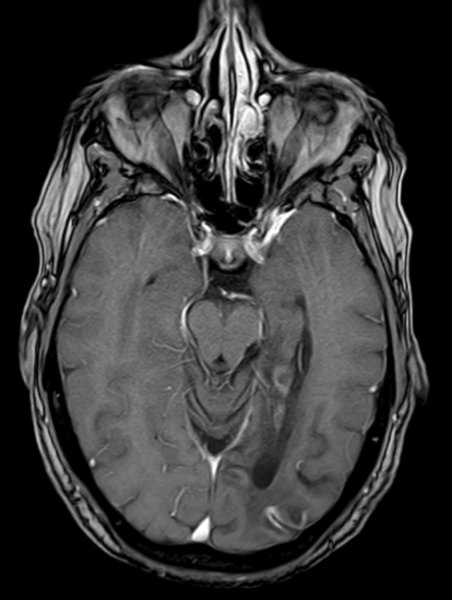

Posteriorinfarkt

Posteriorinfarkt T1 mit KM - axial